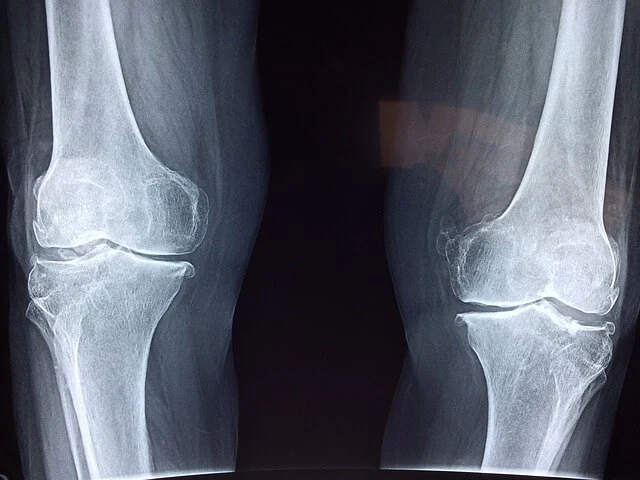

무릎 관절은 우리의 몸의 무게를 버티는 역할을 해주는 중요한 부위이지만, 일상생활에서 많이 사용하기 때문에 우리나라 어르신 중 많은 분들이 무릎 관절 통증에 시달리고 있습니다.

스스로 걷기 조차 어려운 퇴행성 무릎관절염은 건강은 물론 삶에도 큰 영향을 미치는데요

📌 (대상질환) 건강보험급여 '인공관절치환술(슬관절)' 인정기준에 준하는 질환자